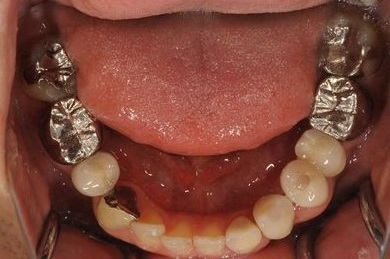

インプラントの症例写真 IMPLANT

骨再生インプラント治療

| 性別/年齢 | 男性 / 34歳 | ||||||||||||||||||||||||||||||||

| 治療方針 | ソケットリフトにて上顎洞を拳上し、インプラント治療を可能にする。 | ||||||||||||||||||||||||||||||||

| 治療内容 | インプラント1本(ソケットリフト)、メタルボンドセラミッククラウン1本 | ||||||||||||||||||||||||||||||||